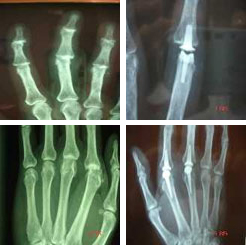

Artrosis de los dedos

Son muy frecuentes los nódulos a nivel de las articulaciones interfalángicas distales (IFD) de los dedos largos conocidos como nódulos de Heberden. Tienen un cierto componente familiar y son mucho más frecuentes en mujeres. Esta patología no tiene tratamiento quirúrgico.

Sin embargo las artrosis a nivel de las articulaciones interfalángicas proximales sí que tienen tratamiento quirúrgico en estadios evolucionados, siendo muy satisfactoria hoy en día la implantación de prótesis de sustitución de la articulación de diferentes características.

También es muy útil el tratamiento de la artrosis ubicada a nivel de la articulación metacarpofalángica mediante prótesis de las mismas características mencionadas anteriormente.